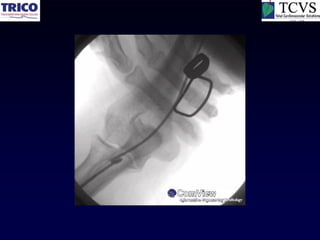

Loop & Perforation